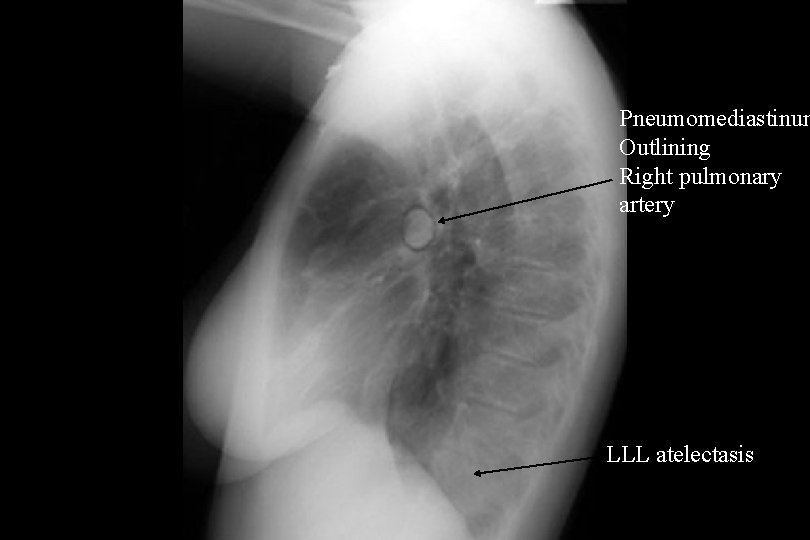

Pneumomediastinum Outlining Right pulmonary artery LLL atelectasis